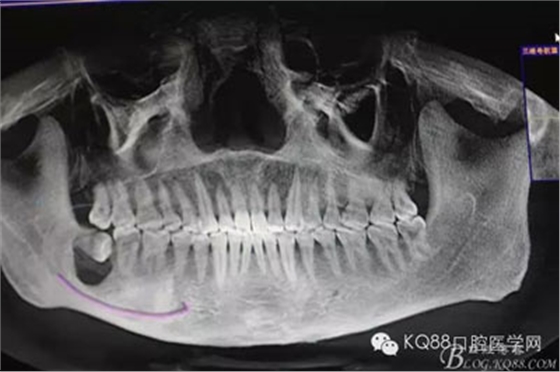

圖2.術(shù)前的CBCT檢查:48下方頜骨橢圓形囊性陰影,下方接近下頜管。

圖3.這張重建的全景片,似乎48就漂浮在囊腔上方,由此感覺(jué)48拔除如同探囊取物一般。